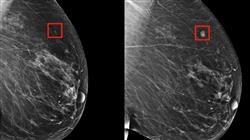

Наследственный рак - это рак, возникающий из-за генетических изменений, унаследованных от родителей. Примерами могут служить наследственный рак молочной железы, наследственный неполипоидный рак толстой кишки и синдром Линча.

В случае наследственного рака клинический генетик может помочь выявить людей с высоким риском развития рака из-за генетической предрасположенности и дать рекомендации по принятию решений о профилактических тестах или медицинских вмешательствах. Клиническая генетика играет важную роль в диагностике, профилактике и лечении детских нефроурологических заболеваний и наследственного рака, улучшая качество жизни пациентов и членов их семей.